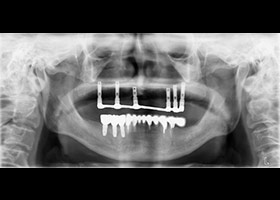

![proimages/case/Artificial_implant/HON09.jpg proimages/case/Artificial_implant/HON09.jpg]()

15.治療完成之全口X光片。